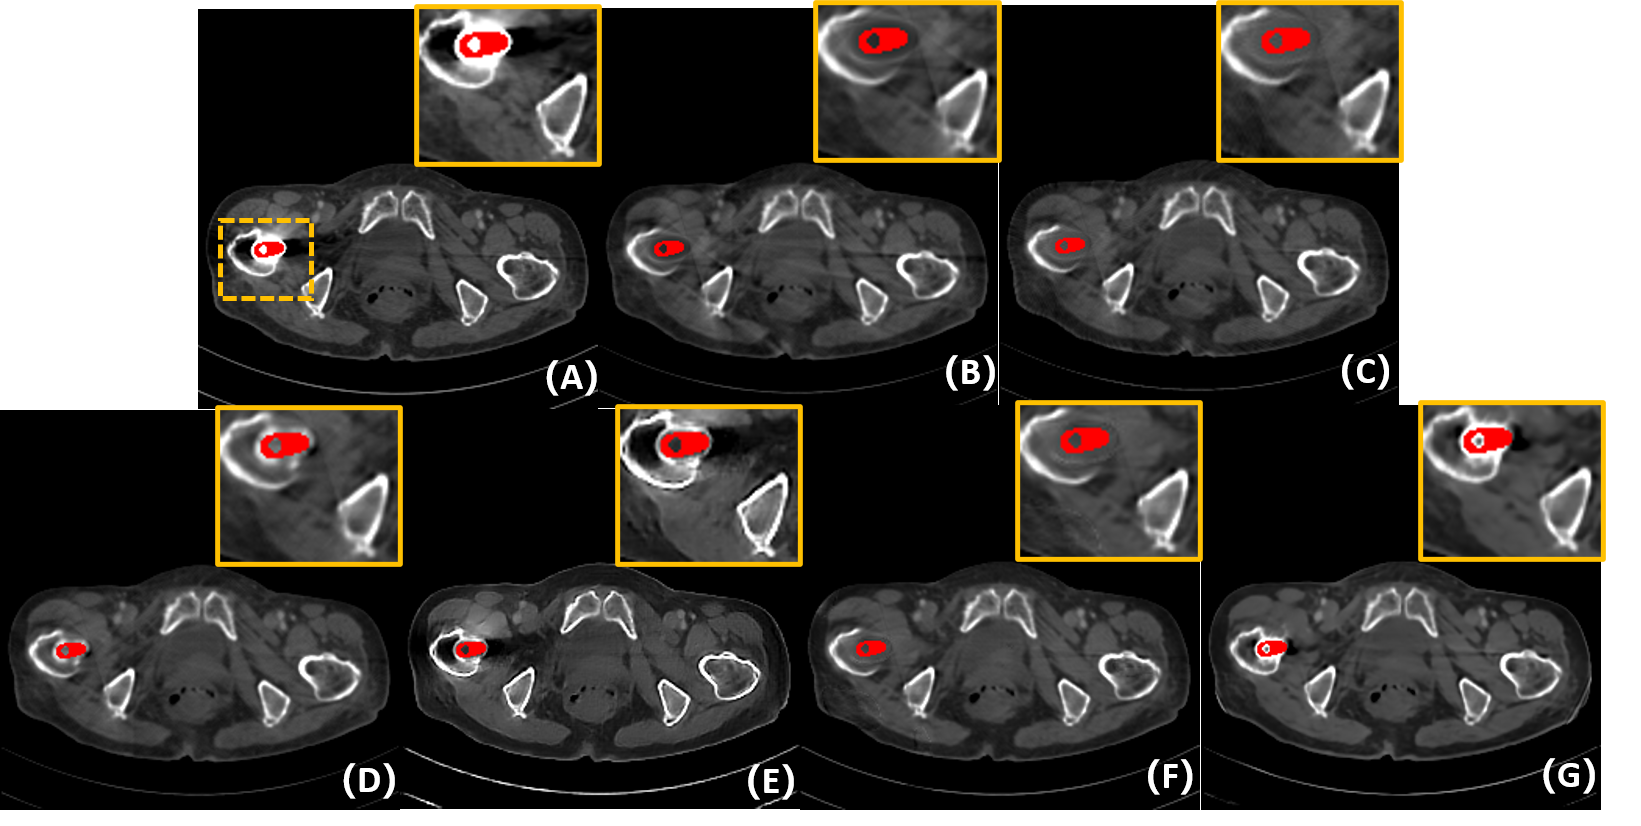

2) Qualitative comparisons: Fig. 6 shows the representative results of different methods on simulated data with different metal sizes. For better visualization, the metal masks are painted in red. Due to the fact that LI and NMAR are interpolation-based methods directly discarding the projection data in metal trace, the metal information is lost and the corrected sinogram cannot keep the continuity at the boundaries of metal trace, leading to blurred tissues around the metals and remarkable secondary artifacts. Although CNNMAR fuses the results of different MAR methods, the improvement is quite limited. ADN achieves better performance on structure recovery around the metal implants than LI, NMAR and CNNMAR, and even DuDoNet in some cases, but it also can be noticed that in the second case (Fig. 6 (F2)), the shadow artifacts are not well suppressed and the details covered by the artifacts are hard to identify. This phenomenon probably lies in that ADN is essentially a post-processing method, which does not leverage the sinogram information. Compared to other methods, DuDoNet and the proposed IDOL-Net have the best performance on artifact reduction, but DuDoNet cannot recover the structures and tissues around the metal well, which can be clearly observed in the magnified yellow boxes in Fig. 6 (G2) and (G3). Our proposed IDOL-Net not only effectively removes most artifacts but also recovers the details better than all the other methods in all cases.

5.4 Experimental results on clinical data

To evaluate the robustness of our IDOL-Net for clinical practice, clinical CT images were tested and Fig. 7 shows the visual comparisons of one representative slice processed using different methods. The metal was segmented by the threshold of 2000 HU and the metal mask is painted in red for better visualization. The test image was normalized to the same range as the training data and the results were obtained using the model trained with simulated dataset used in the previous subsection. In Fig. 7 (A), the metal leads to severe artifacts, which covers some tissues, especially near the metal. It is observed that LI, NMAR and DuDoNet cannot retrieve the tissues around the metal, but due to the utilization of dual-domain information, DuDoNet outperforms most methods in artifact reduction. Since the shadow artifacts around the metal is very heavy, ADN cannot do much about this, which is similar to the situation in simulated dataset. It is observed that IDOL-Net suppresses most of the metal artifacts and effectively preserves the anatomical structures around the metals, which demonstrates its potential for real clinical application.